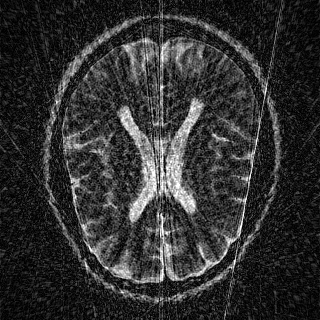

This article presents a novel undersampled magnetic resonance imaging (MRI) technique that leverages the concept of Neural Radiance Field (NeRF). With radial undersampling, the corresponding imaging problem can be reformulated into an image modeling task from sparse-view rendered data; therefore, a high dimensional MR image is obtainable from undersampled $k$-space data by taking advantage of implicit neural representation. A multi-layer perceptron, which is designed to output an image intensity from a spatial coordinate, learns the MR physics-driven rendering relation between given measurement data and desired image. Effective undersampling strategies for high-quality neural representation are investigated. The proposed method serves two benefits: (i) The learning is based fully on single undersampled $k$-space data, not a bunch of measured data and target image sets. It can be used potentially for diagnostic MR imaging, such as fetal MRI, where data acquisition is relatively rare or limited against diversity of clinical images while undersampled reconstruction is highly demanded. (ii) A reconstructed MR image is a scan-specific representation highly adaptive to the given $k$-space measurement. Numerous experiments validate the feasibility and capability of the proposed approach.